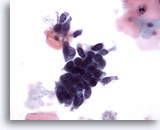

Adenocarcinoma in situ

A strip of endocervical cells exhibiting pseudostratification and finely vacuolated cytoplasm with indistinct cytoplasmic borders. Architecture is disrupted although cells are still attempting to maintain a glandular configuration. Note increased N/C ratio and the variable presence of nucleoli. Biopsy – AIS – 60x